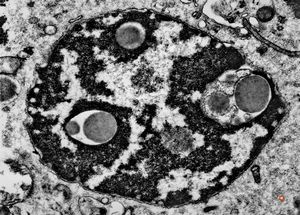

F,52y. | intranuclear inclusions - plasmocytoma